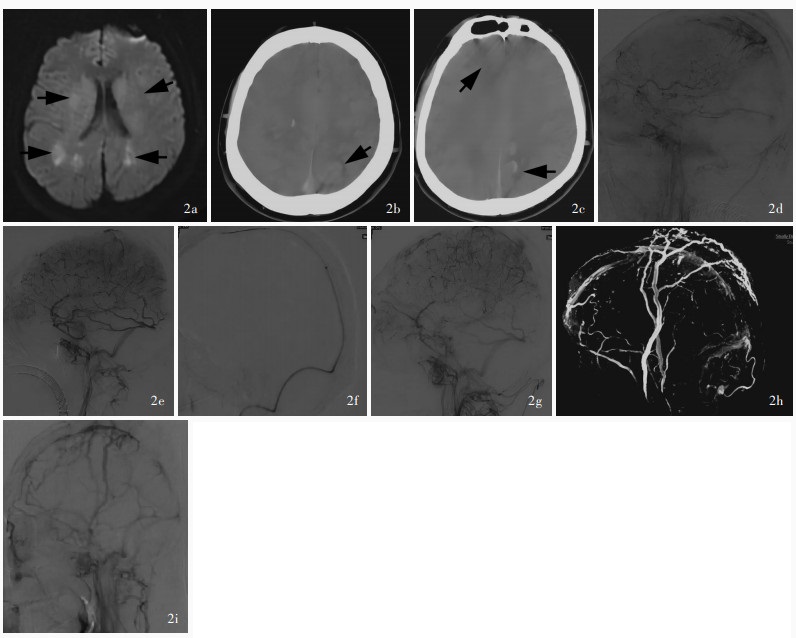

孙刘严, 郭新宾, 魏森, 杨震, 王晶晶, 管生. 支架取栓联合局部溶栓治疗重型颅内静脉窦血栓形成临床研究. 介入放射学杂志, 2021, 30: 643- 646.

Sun LY, Guo XB, Wei S, Yang Z, Wang JJ, Guan S. Stent ‐ retrievers combined with local thrombolysis for the treatment of severe cerebral venous sinus thrombosis: a clinical study. Jie Ru Fang She Xue Za Zhi, 2021, 30: 643- 646.